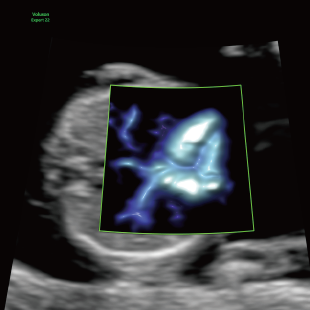

Voluson Expert 22®(GEHealthcare)という産婦人科領域におけるハイエンド超音波診断装置を使用しています。 従来機種と比べ、より高精細な画像描出性能と高度な解析機能を備えており、 胎児の発育や形態をより詳細に観察することが可能です。